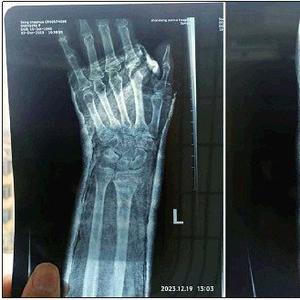

多人上下班途中摔伤

2023年12月12日清晨,张秀梅(化名)像往常一样,骑着电动车赶往4公里外的单位,她是这里的一名保洁阿姨。熟悉的道路因头一天降下的雪变得非常滑,拐弯的时候张秀梅摔倒了,触地的左手传来一阵剧痛。随后,她被确诊为左手骨折,“自费将近两千元”进行了保守治疗——这些费用相当于她大半个月的薪资。而今,打着石膏的左手“完全不能动”,张秀梅在家调养,生活起居由丈夫照顾。

相似的事故还在发生。2023年12月20日傍晚,莱芜区一家工厂的女工李佳惠(化名),从厂门口的车棚里推出自己的电动车。连日严寒,车棚前的路面仍有薄冰,厂里往冰面上撒了些沙子来防滑。可李佳惠的电动车还是打滑了,才骑出去一两米她便倒下了,“疼得跪在地上,左脚完全动不了”。后来,李佳惠被确诊为左脚脚踝骨裂,“不用动手术,但需要在家休养两三个月”。她原本便收入不高,每月工资不过三千多元,而今无法出门工作,家中越发捉襟见肘。